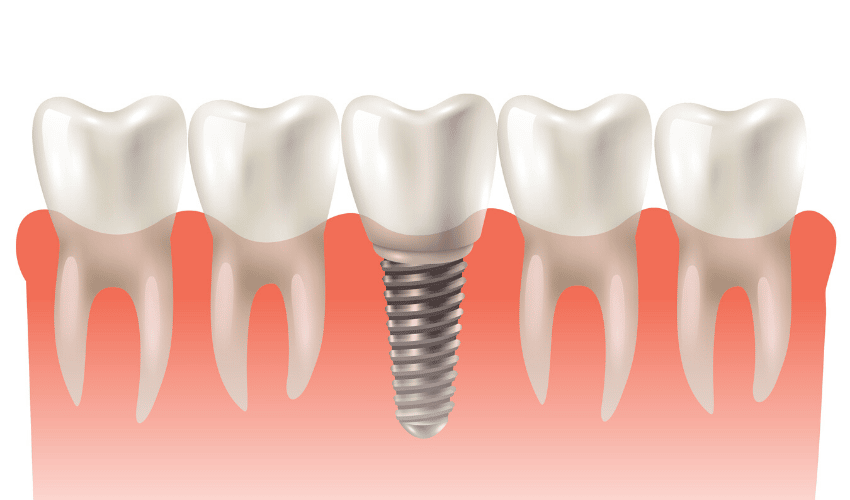

Dental implants have been becoming more and more popular in the field of restorative dentistry, which owes to the amazing benefits that it has overdentures. As per a report published by Reuters, over 3 million people in the US had dental implants in 2016 and the number has increased by half a million every year since then.

While the ratio of implants to dentures is still low among patients, considering the recency of implants and the cost associated with it, we must admit that dental implants have boomed in dentistry. Why? Let’s take a look at the 5 reasons why dental implants are the best dental restorations.

Dental implants are a permanent solution to your missing teeth. Even when you lose all your natural teeth, chances are that your implants would be the last ones to fall off. This is because dental implants are designed and implanted to last over 30 years. Thus, once you replace a missing tooth with an implant, you need not worry about that tooth for the rest of your life!

5. Natural look and feel

Dental implants look completely natural. Once healed, they feel absolutely natural as well. Overall, you would eventually forget over time that you have an artificial implant in your mouth because of how natural the look, feel, and functionality of dental implants.